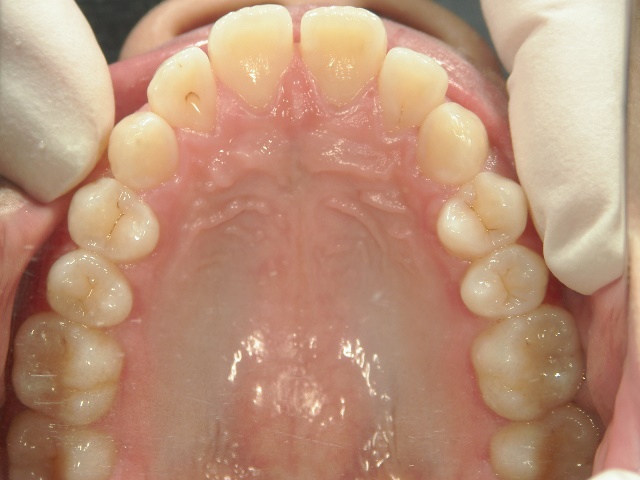

矯正歯科 治療前